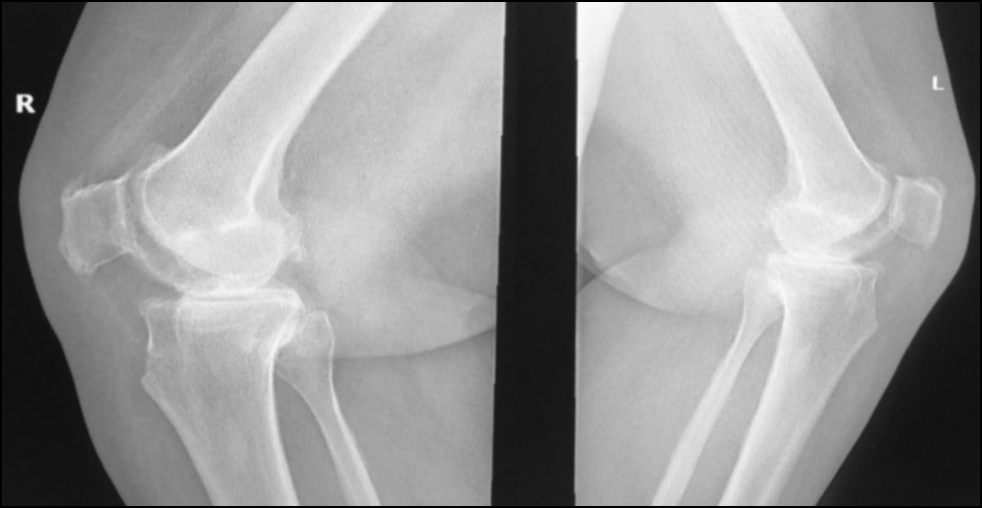

CASE 2. PATIENT 3

Age: 67 years.

Sex: Female.

Diagnosis: Bilateral advanced knee osteoarthritis.

Procedure: Bilateral simultaneous knee arthroplasty.

Associated illnesses: DM and hypertension.

Postoperative follow-up: No postoperative complications were encountered.

Length of hospital stay: 6 days.

Radiological assessment (Fig. 15–18)

Fig. 15. Ap preoperative x-ray showing bilateral knee osteoarthritis.

Рис. 15. Предоперационная рентгенограмма с двусторонним остеоартритом коленного сустава.

Fig. 16. Lateral preoperative x-ray right and left knees showing osteoarthritis.

Рис. 16. Предоперационная боковая рентгенограмма правого и левого колена с признаками остеоартрита.